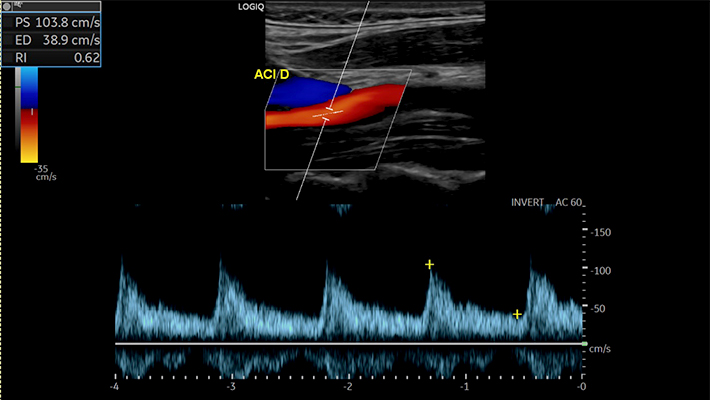

- триплексным — дополняет картину цветным отображением кровотока, что облегчает оценку сужений и деформаций.

- гемодинамические характеристики: скорость, направление и равномерность кровотока;

Заключение содержит описание состояния сосудов и объективные количественные показатели (скорость кровотока, степень стеноза, толщина КИМ). Оно не является диагнозом, а используется лечащим врачом — неврологом, терапевтом или сосудистым хирургом — для уточнения причин симптомов и выбора тактики лечения.